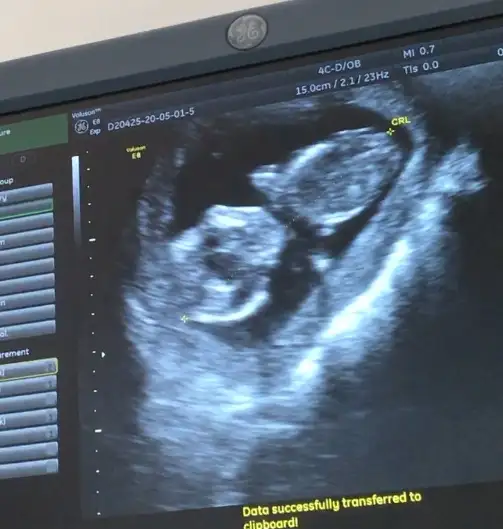

14 haftalık renkli ultrason var ama yine örttüKız yönünde12 olsa teyit ederim

Bi bakim onada14 haftalık renkli ultrason var ama yine örttü![]()

oda buBi bakim onada![]()